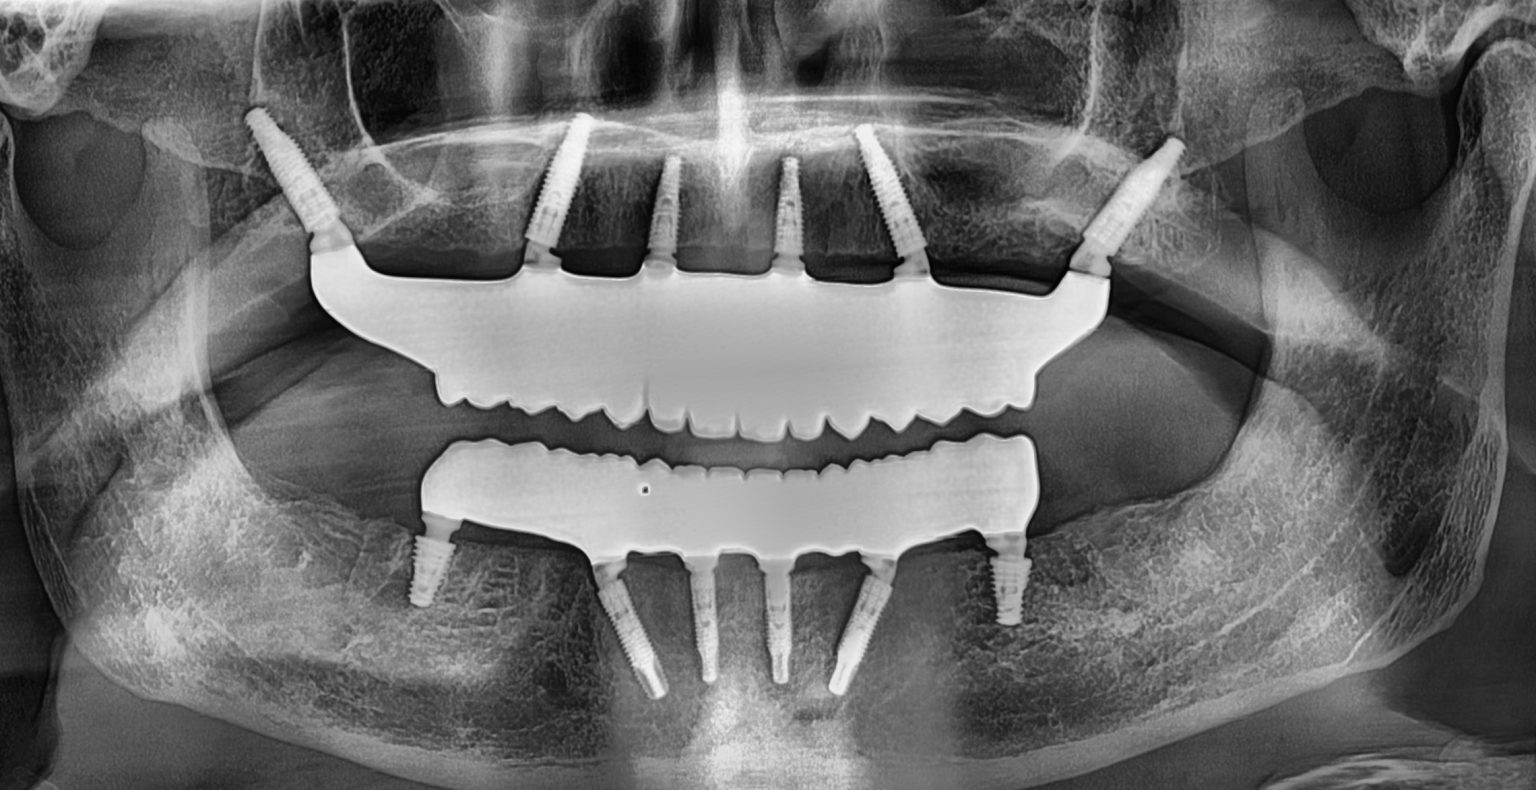

Teeth-In-A-Day is a revolutionary dental implant procedure that allows you to walk into the clinic with missing or failing teeth and leave the very same day with a beautiful, fully functional smile. In just one appointment, our expert implant dentist can place four strategically positioned dental implants and attach a fixed bridge, restoring your confidence instantly.

In its most advanced application, Teeth-In-A-Day can replace an entire set of teeth- upper, lower, or both- with implants and a non-removable set of natural-looking teeth in just 24 hours. This technique can also be used for replacing a single missing tooth without the lengthy wait times of traditional implants.